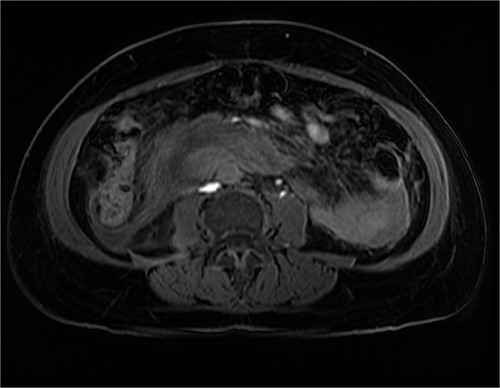

After further discussion with the reporting radiologist, a magnetic resonance imaging (MRI) was performed, which confirmed the presence of an acute periduodenal hematoma surrounding D2 and D3, lying in the retroperitoneal space, anterior to the right perirenal space. Etiology was uncertain. No abnormal enhancement within the bowel to suggest a bowel wall lesion or infiltrating mass (Figs 3 and 4).

MRI abdomen, coronal view. T2 hypointense, T1 iso to hyperintense material surrounding D2/D3 without enhancement in keeping with hemorrhage. No vascular or bowel wall lesion identified.